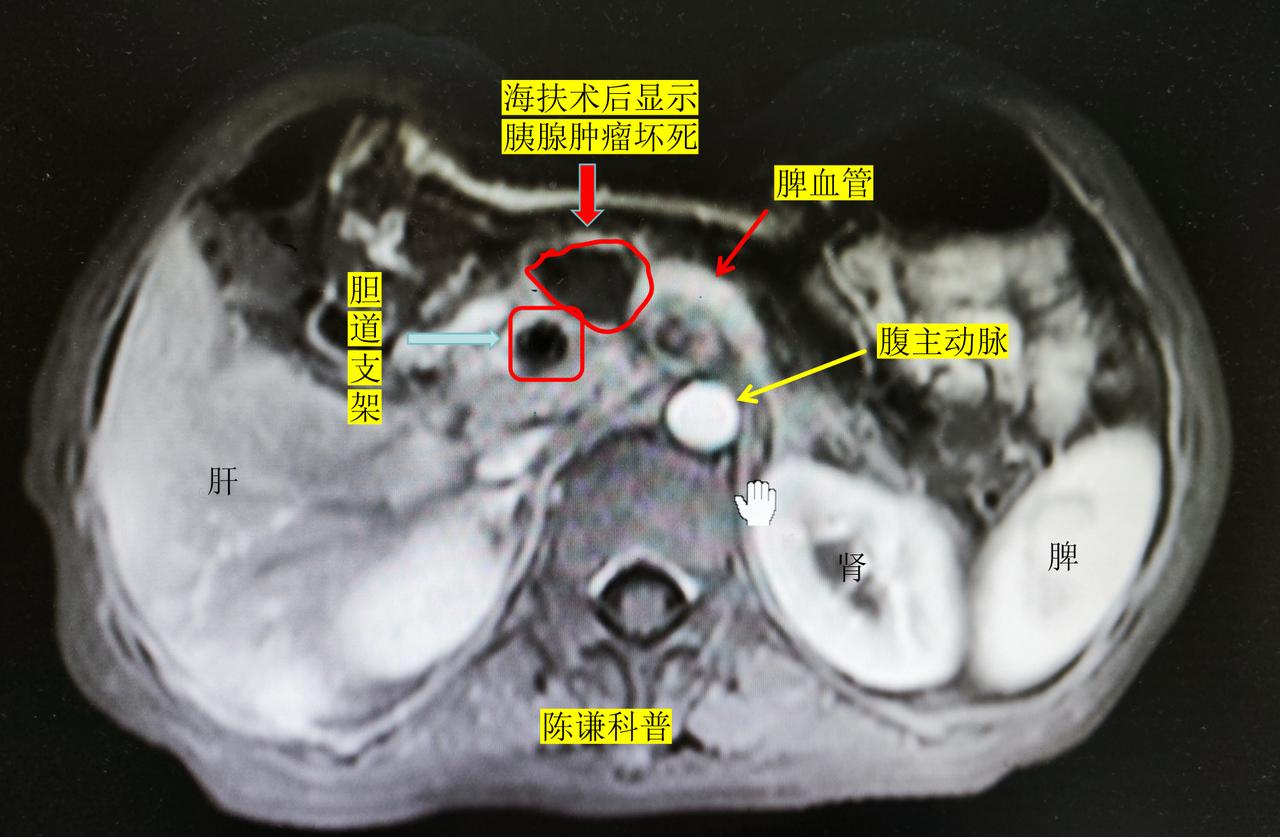

胰腺癌晚期患者如何缓解疼痛? 胰头癌是胰腺癌中最常见的类型,由于肿瘤很容易侵犯胆总管导致黄疸,并且肿瘤后方就是血管,所以很多中晚期胰腺癌都放置了胆道支架引流减黄,同时肿瘤侵犯血管和腹膜后淋巴结而失去了手术机会,对于这样的胰腺癌,大多数医院的治疗方案主要是化疗和临床试验,但是效果不理想。海扶刀治疗是一种微无创的治疗方法,可以对有胆道支架,侵犯血管,腹膜后淋巴结转移的肿瘤进行消融。 今天分享的是一名来自黑龙江的晚期胰腺癌患者,病人51岁,因黄疸在当地医院检查确诊胰腺癌,做了胆道支架,经过化疗后肿瘤有进展,伴有后腰部疼痛,然后至我们中心海扶治疗。 治疗前增强CT可以很清晰的显示,肿瘤已经包饶了腹腔干动脉,腹膜后淋巴结肿大,病灶前方是胃,右侧是十二指肠和胆道支架,后方是血管,右侧是肠道,但是经过我们海扶治疗后,肿瘤完全灭活,对血管,胆道支架没有任何影响,周边组织都保护很好,术后患者疼痛也得到明显改善。 所以,对于放置了胆道支架或者十二指肠支架的胰腺癌,肿瘤侵犯血管患者,海扶刀治疗也是安全有效的,能够达到减瘤止疼,提高生活质量,延长生存期的效果。海扶刀